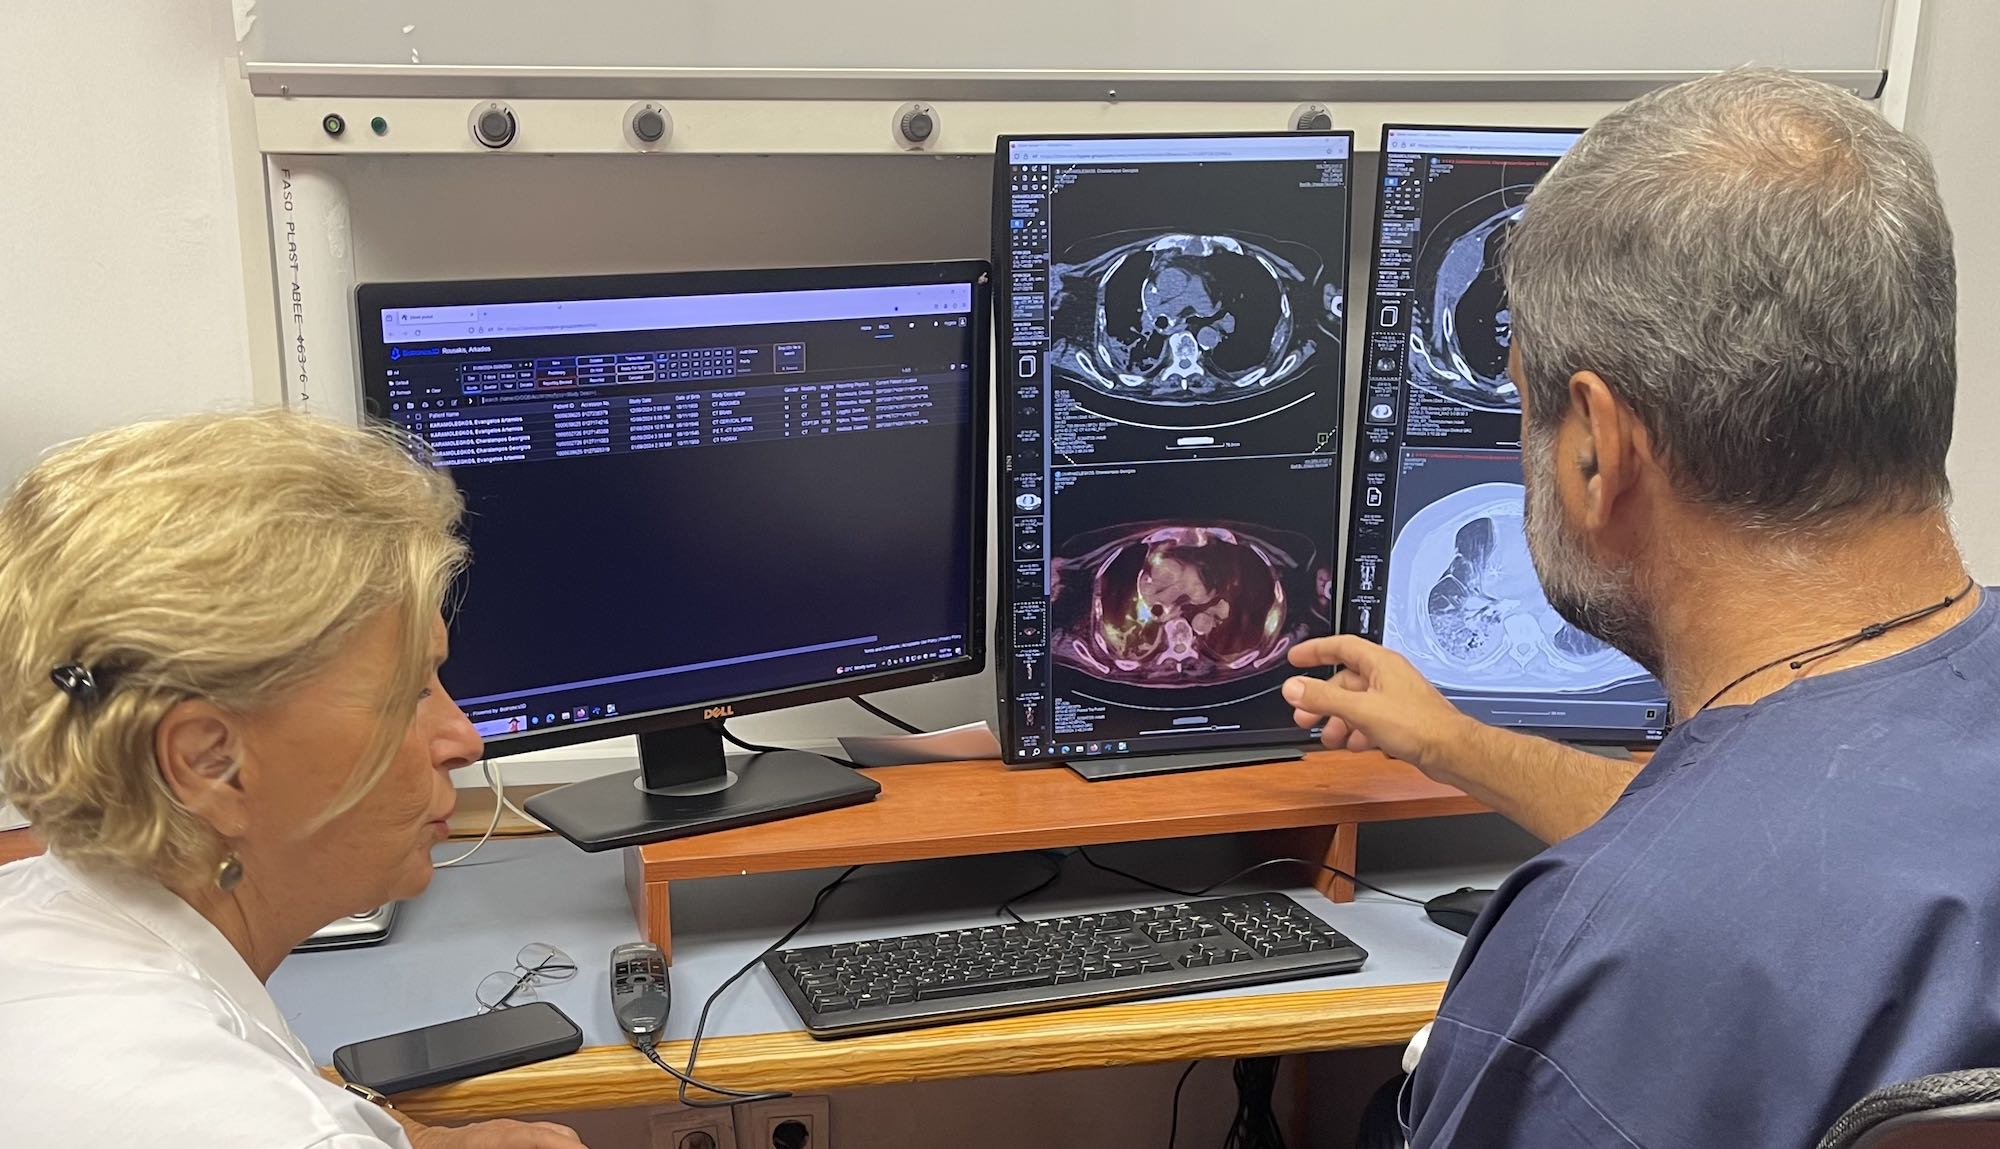

Η διαδικασία της διάγνωσης απαιτεί τόσο τεχνική επάρκεια όσο και ανθρώπινη ευαισθησία. Χρησιμοποιούμε τις πιο σύγχρονες μεθόδους και τεχνολογίες για να εντοπίσουμε την αιτία των συμπτωμάτων σας, ενώ παράλληλα διασφαλίζουμε ότι κάθε ασθενής νιώθει κατανοητός και σεβαστός καθ' όλη τη διαδικασία.

Τελευταίας Γενιάς Εξοπλισμός

Επενδύουμε συνεχώς σε τελευταίας γενιάς εξοπλισμό, ώστε η διάγνωση και η θεραπεία σας είναι όσο το δυνατόν πιο ακριβείς και αποτελεσματικές.